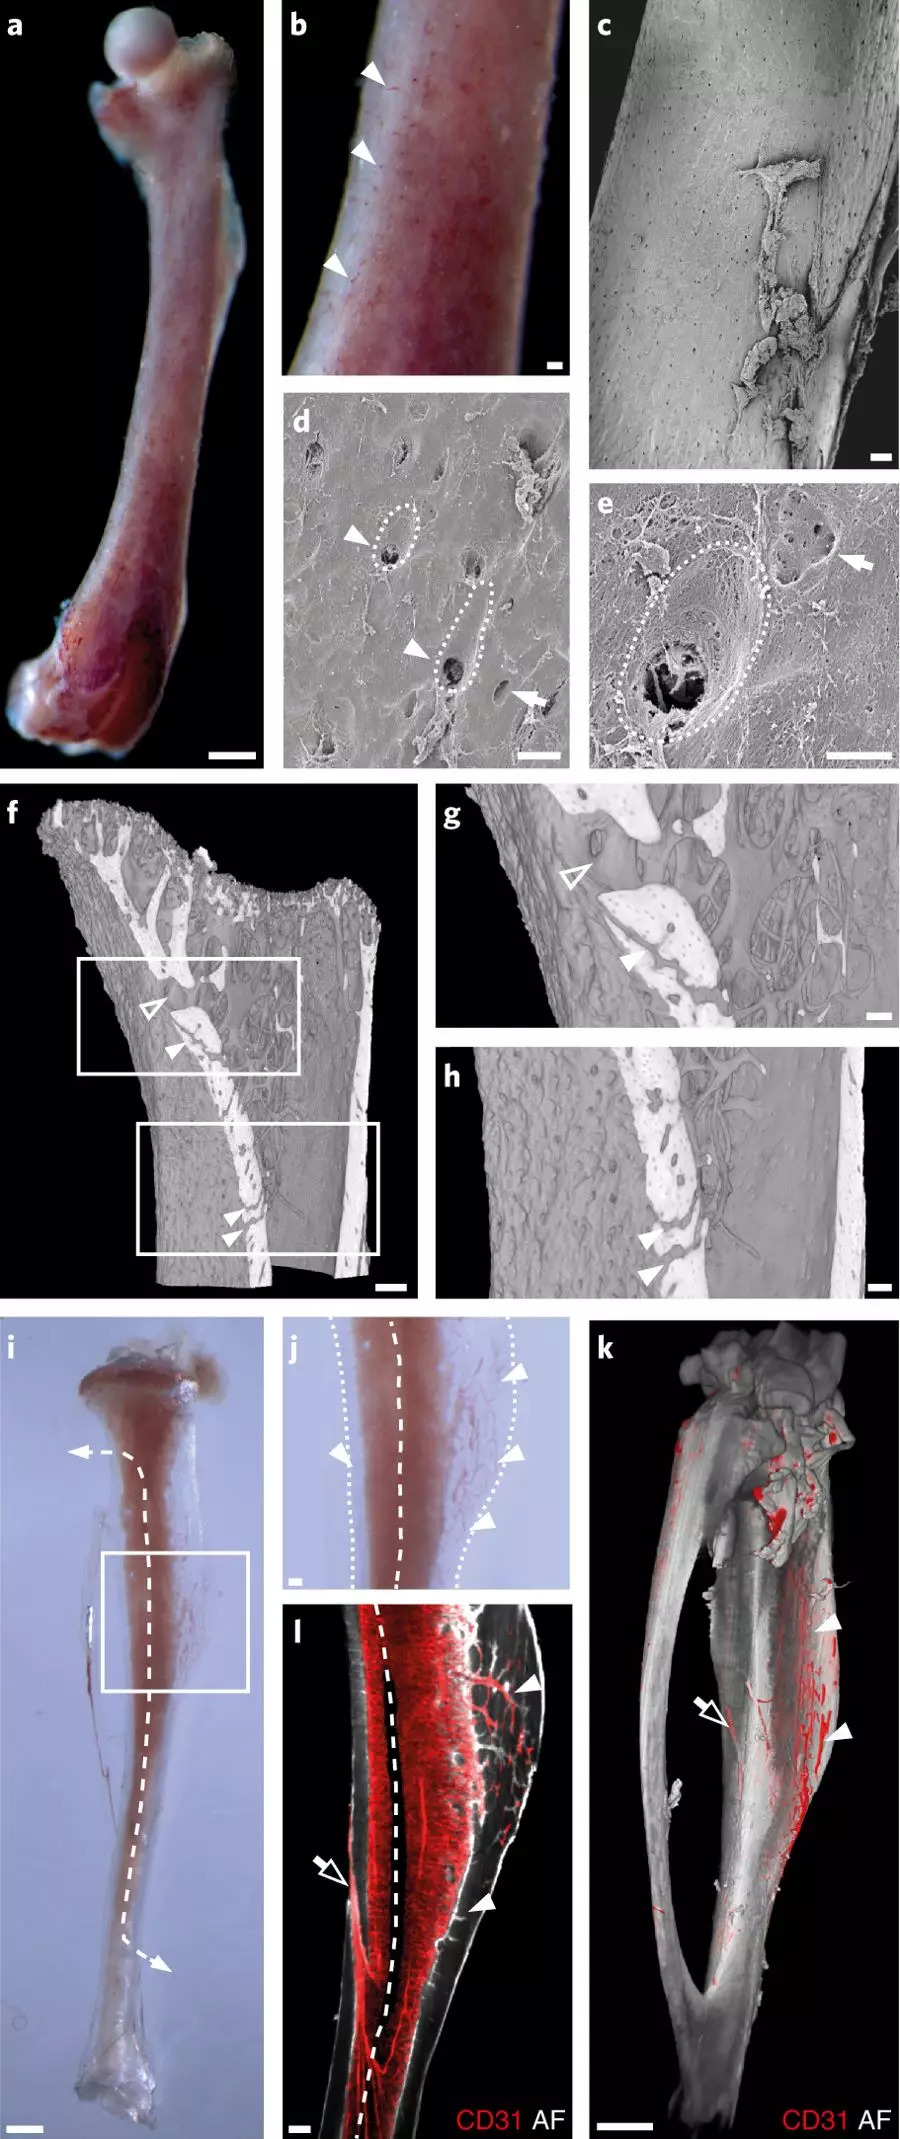

Gunzer的团队做出这一发现的起始是利用化学物质使实验小鼠的骨骼变透明,通过观察这些透明的骨骼,发现有细细的红色微小血管从骨干中穿过。

实验动物的小腿骨大概只有一根火柴那么大,但是在这样一根细小的骨头里,他们发现了大约一千根这样的细血管,并将其命名为跨皮质血管。在此之前,学界一直认为只有少量血管的末端或中段会跨越骨骼进入骨腔内,但在这个新发现中,研究团队看到这些跨皮质血管覆盖了整个骨骼,并且给骨骼供应了大部分血液。

图片来自 nature metabolism

人体当中也存在类似的跨皮质血管,该研究团队在小块的人大腿骨中也发现了它们的存在。由于还有其它的血管给人体骨骼供血,因此跨皮质血管可能占总循环量的比例较小,不过到目前为止还没有人计算过人体骨骼当中到底有多少这样的血管存在。